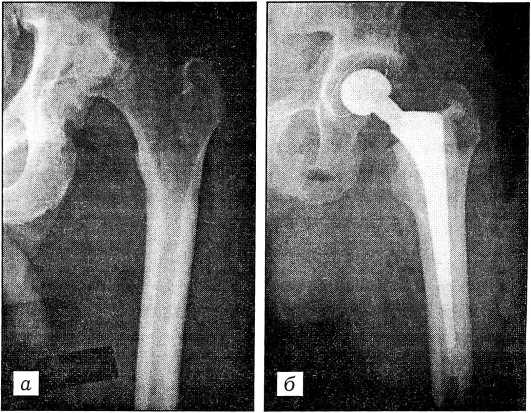

Рис. 3. Рентгенограммы тазобедренного сустава больной, перенесшей медиальный перелом шейки бедра с последующим лизисом головки. а — до операции; б — через 2 года после тотального эндопротезирования эндопротезом ИСКО-РУДН.

Приготовленный костный цемент вводили с помощью специального шприца и пистолета, при этом всегда использовали низковязкий цемент. Введенный в бедренный канал цемент уплотняли специальными инструментами или влажной салфеткой. Затем в канал вводили ножку эндопротеза. Введение должно осуществляться плавно и строго по оси бедра с некоторым отклонением к задней стенке (большому вертелу). Последние 10—15 мм ножки обычно погружали посредством легких ударов молотка по установочному инструменту. Шейку эндопротеза располагали в нейтральном положении или с незначительным отклонением кпереди (антеверсия). Ножки с воротниками плотно прилегали к костному опилу шейки без костного цемента между ними (ножки фирмы «Синко», ИСКО-РУДН, Мовшовича—Гаврюшенко) (рис. 3). После полного погружения ножку удерживали в таком положении до окончания полимеризации костного цемента. (В нашей практике были случаи, когда введенная в цемент и не удерживаемая ножка выталкивалась из канала расширяющимся цементом на 10-20 мм.) Остатки костного цемента вокруг ножки удаляли пластмассовыми ложками и скальпелем.